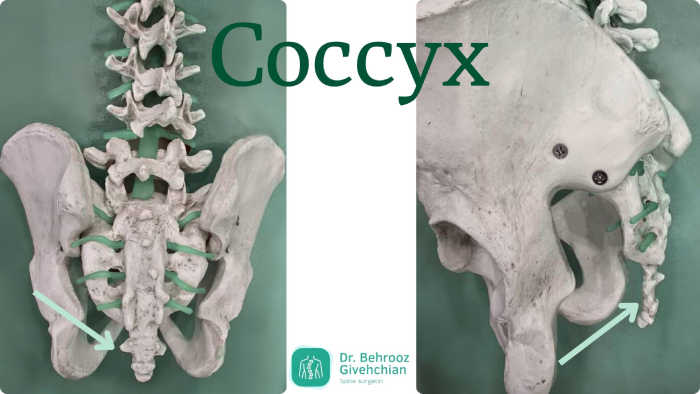

دنبالچه کجاست و چه نقشی دارد؟

برای درک بهتر علتها و درمانهای درد دنبالچه، لازم است ابتدا با ساختار و عملکرد این بخش از ستون فقرات آشنا شوید. دنبالچه در پایینترین قسمت ستون فقرات، درست در بالای مقعد قرار دارد و از چند مهرهی کوچک تشکیل شده که معمولا در بزرگسالی به هم جوش خوردهاند. این استخوان کوچک در ظاهر ساده به نظر میرسد، اما نقش مهمی در حفظ تعادل بدن هنگام نشستن و حرکت دارد. علاوه بر آن، دنبالچه محل اتصال تعدادی از رباطها و عضلات کف لگن است که در پایداری بدن و کنترل حرکات لگن و نشیمنگاه نقش اساسی دارند. به همین دلیل، هرگونه التهاب، ضربه یا فشار بیش از حد بر این ناحیه میتواند به بروز درد دنبالچه و اختلال در فعالیتهای روزمره منجر شود.